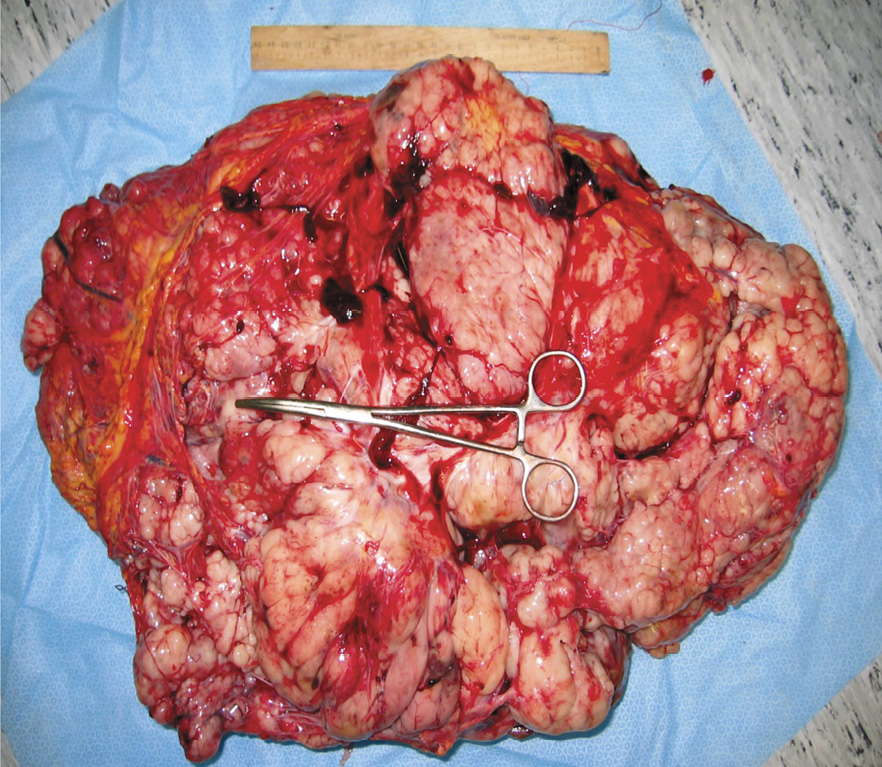

21.12.2005 больная оперирована левосторонним торакоабдоминальным доступом. При ревизии практически всю брюшную полость занимала гигантская многоузловая опухоль, представляющая собой опухолево измененный большой сальник. От опухоли был свободен только правый латеральный канал, куда были смещены все петли тонкой и ободочной кишки. Нижний полюс опухоли располагался в малом тазу, верхний полюс опухоли прорастал диафрагму и смещал ее до уровня III ребра слева. Опухоль прорастала париетальную брюшину передней брюшной стенки, при этом медиальный край опухоли подрастал к левой доле печени. На серозной оболочке подвздошной кишки и брюшине правого латерального канала определялись множественные метастазы до 0,5 см. Больной выполнено удаление опухоли большого сальника с атипичной резекцией левой доли печени и спленэктомией. Вес удаленной опухоли составил 13 кг (рис. 3). Послеоперационный период протекал без осложнений.

Рис. 3. Макропрепарат удаленной гастроинтестинальной стромальной опухоли большого сальника с резецированным участком левой доли печени и селезенкой.